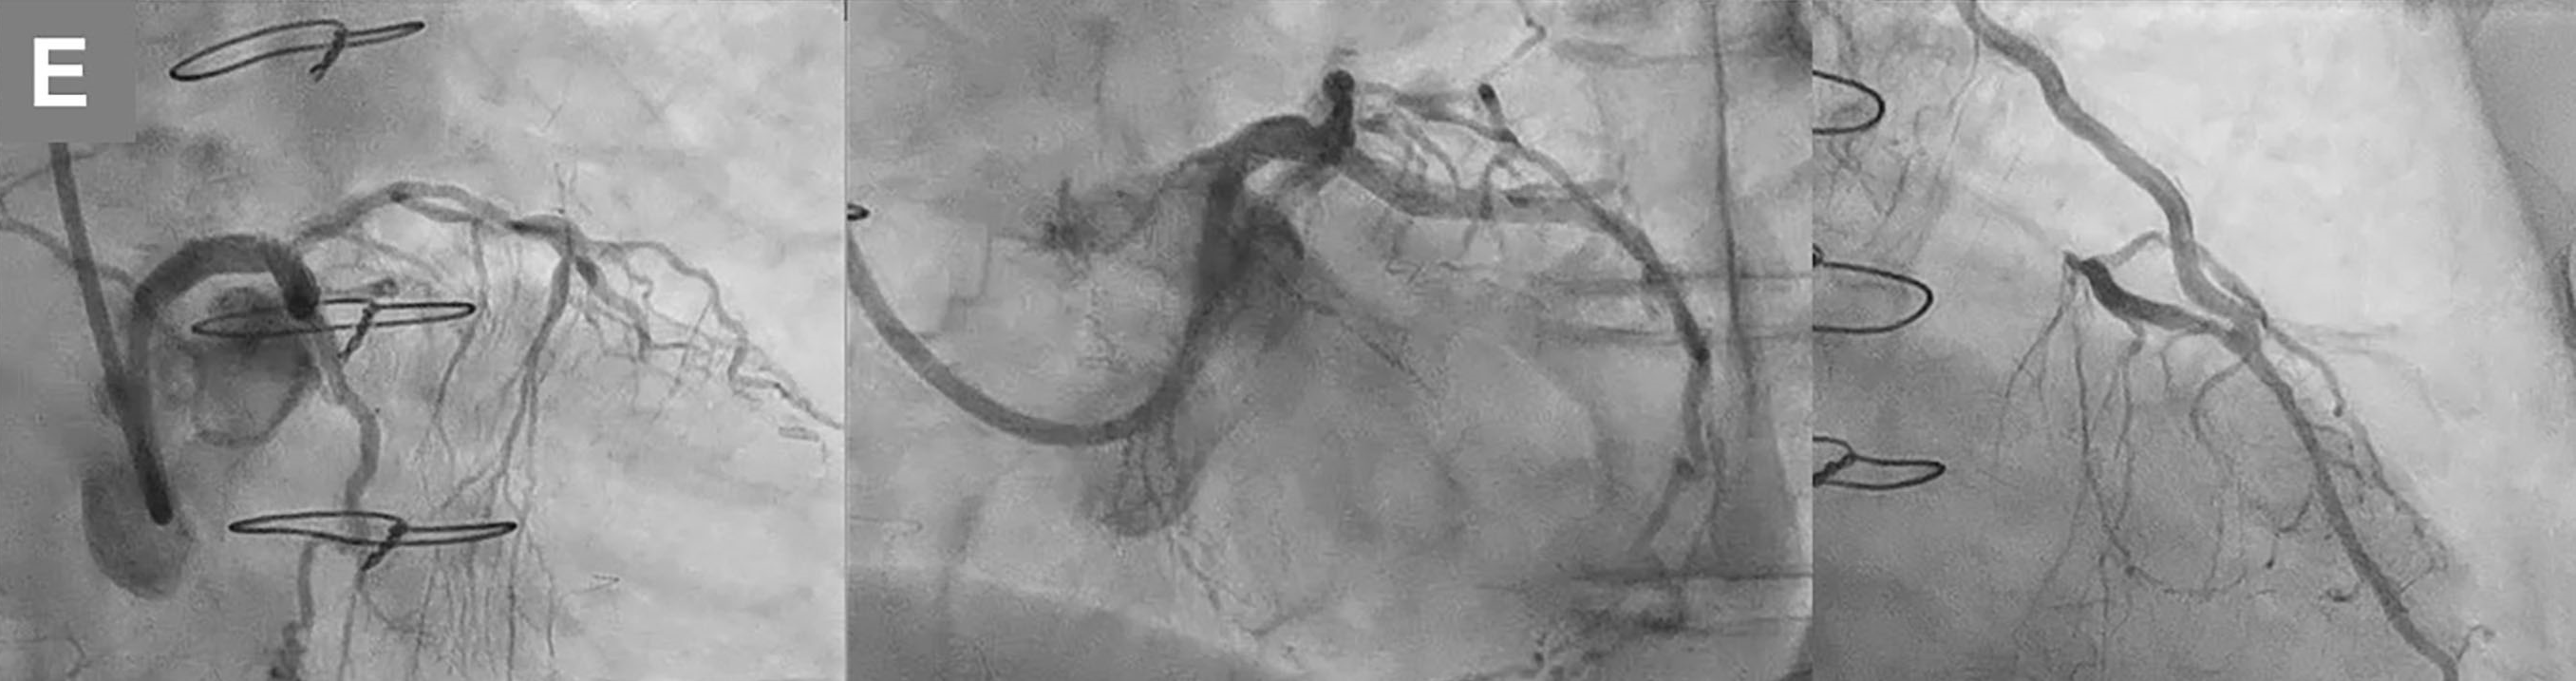

Since CCTA indicated a blunt-type LM chronic total occlusion (CTO) in the straight route that was composed of fibrous tissue and connected to distal bifurcation (Figure A), percutaneous coronary intervention (PCI) for LM-CTO was performed with contralateral injection from the LITA-LAD. A 7-French AL2.0 SH guide catheter (Heartrail II, Terumo) was engaged in the LM and a tapered stiff guidewire (X-treme XTA, Asahi Intec) penetrated the CTO lesion and crossed to the LCX (Video 3). Intravascular ultrasound confirmed the guidewire’s penetration of the true lumen. (Figure C; Video 4). A 3.5 x 22-mm zotarolimus-eluting stent (Resolute Onyx, Medtronic) was implanted from the LM ostium to the proximal LCX (Figure D-a). Proximal optimization with a 4.0-mm balloon (Figure D-b), and final kissing balloon inflation with 3.5 and 2.5-mm balloons (Figure D-c) followed. Complete antegrade flow from the LM to LCX and good collateral flow into the distal RCA was achieved (Figure E-a, b; Videos 5 and 6). The proximal to middle LAD lesions were left untouched due to sufficient flow from the LITA-LAD graft (Figure E-c). Informed consent was obtained from the patient prior to all procedures.